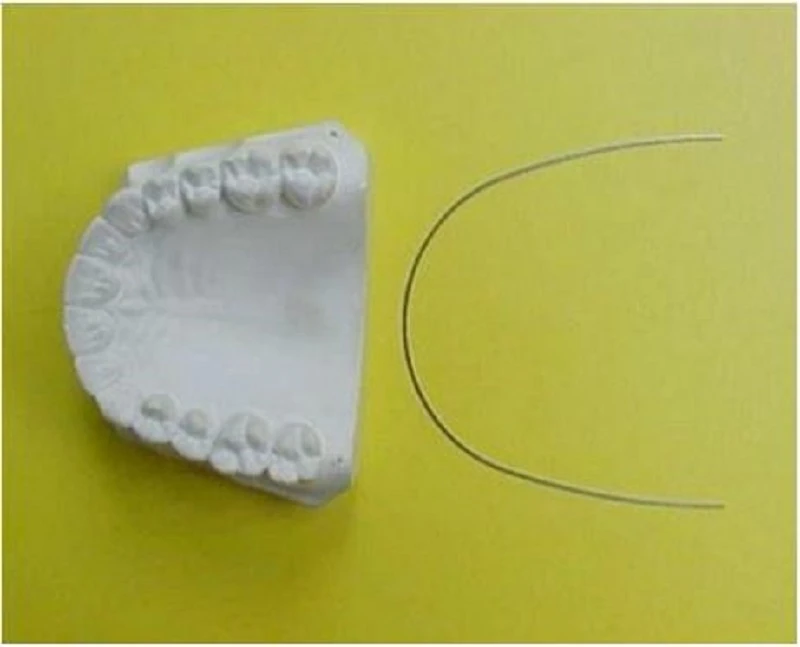

Ta có thể sử dụng mẫu nghiên cứu hàm dưới để xác định hình dạng hàm dưới. Bước đầu tiên để chọn dây cung chuẩn là xác định xem hàm dưới có hình tròn, nhọn hay vuông. Có thể sử dụng Template bán sẵn để phục vụ mục đích này.